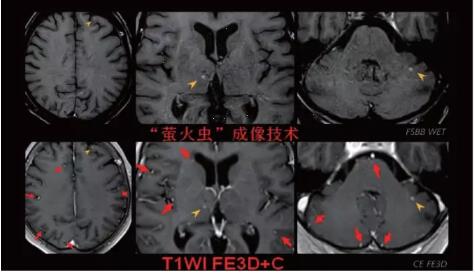

“螢火蟲(chóng)”成像技術(shù)——見(jiàn)所未見(jiàn) 微小腫瘤無(wú)處遁藏

此技術(shù)主要用于神經(jīng)系統(tǒng)惡性腫瘤,以及其他腫瘤腦轉(zhuǎn)移瘤篩查。傳統(tǒng)情況下做腫瘤腦轉(zhuǎn)移篩查,很容易漏掉5mm以下小病灶,臨床發(fā)現(xiàn)后干預(yù)治療比較晚,要實(shí)現(xiàn)2mm高空間分辨率和超薄層全腦掃描在保證信噪比的情況下需要很長(zhǎng)時(shí)間大概十多分鐘,而且薄層增強(qiáng)序列顱內(nèi)血管呈高亮信號(hào),會(huì)干擾顱內(nèi)小病灶的觀察,血管和小病灶區(qū)分困難。佳能”螢火蟲(chóng)”成像技術(shù)既可以實(shí)現(xiàn)高空間分辨率和超薄層(最薄可實(shí)現(xiàn)0.2mm)全腦掃描,掃描時(shí)間短,2-3分鐘即可實(shí)現(xiàn)全腦3D掃描,同時(shí)避免了血管高亮信號(hào)的干擾,對(duì)顱內(nèi)原發(fā)或繼發(fā)的微小腫瘤檢查有重大意義。“螢火蟲(chóng)”成像技術(shù)具有磁敏感效應(yīng),對(duì)于亞急性血敏感敏感,可以區(qū)分出血和強(qiáng)化的腫瘤。